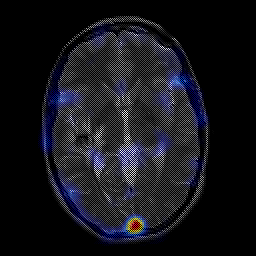

overlay -- Slice #13

[Home][Help][Clinical] Slice 13